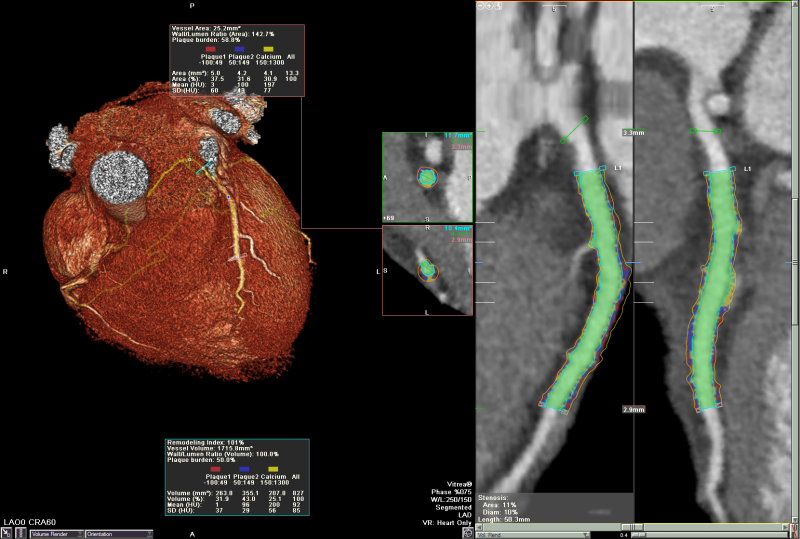

VitreaTM 產(chǎn)品為醫(yī)師提供處理分析2D, 3D和4D醫(yī)學(xué)影像的全套工具, 同時支持多種 設(shè)備 - CT, MR, XA, PET, US, SPECT. 特別在心臟科, 神經(jīng)科, 腫瘤科與介入治療方面 提供了豐富而有針對性的應(yīng)用, 為醫(yī)療專家在手術(shù)計劃與救治病患時提供更多幫助.